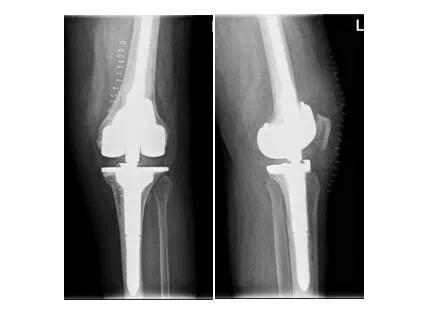

今年68岁的胡阿姨来自青州农村,2016年前因做膝关节骨性关节炎,在当地医院实施了人工膝关节置换术。近4个月来,胡阿姨出现左膝部疼痛、跛行,活动受限,膝关节活动受限。随着疼痛逐渐加重,在当地医院治疗均未能解决,经打听后来到我院关节外科二区就诊。主任医师张益民、副主任医师曹学军等接待了她,经全面、系统检查,诊断胡阿姨的关节在初次置换手术后假体发生了松动并伴有严重的骨量流失。考虑到胡阿姨年事已高,且伴有严重的骨量流失,如果采取保守治疗需要长期卧床,身体各项指标都会受到严重影响,不仅不能保证以后的生活质量,还有可能引发肺部感染、静脉血栓形成、褥疮等并发症。因此,关节外科二区医师团队决定为胡阿姨实施左侧人工全膝关节翻修术。

该人工全膝关节翻修手术比初次置换手术难度系数大且复杂,风险高、创伤大,而且患者骨缺损严重,这为手术又增添了一层难度。为此医师团队决定先行膝关节3D打印技术,打出一个1:1的膝关节模型,先在模型上面完善手术的步骤,以确保手术过程精准又顺利进行。

医师团队充分讨论病情,研讨最佳治疗方案,完善一切术前准备工作后,在科室专家团队的通力配合下,成功为胡阿姨实施了左侧人工全膝关节翻修手术。